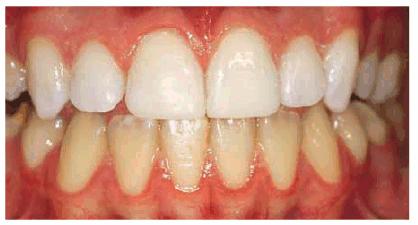

chromogenic foods, and beverages (Figures 16-16A 16-16B 16-17A, and 16-17B). Although these types of stains

Figure 16-16A: Some teeth darken over time from chromagenic foods. Some patients' teeth are just naturally yellow.

Figure 16-16B: Whitening of the maxillary teeth using 10% carbamide peroxide in a custom tray results in a more pleasing smile. This patient is now interested in closing the spaces.

Figure 16-17A: Some teeth darken through natural aging.

Figure 16-17B: Whitening of the maxillary teeth using 10% carbamide peroxide in a custom tray produces a normal progression of color from gingival to incisal edge but offers a more pleasing, younger look to the patient.